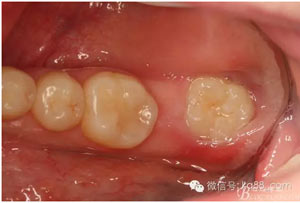

圖3。閉口位,27與38有咬合接觸。因此,保留38、拔除37.防止囊性變進一步擴大。

圖4.咬合面觀察。37間隙變小,牙齒 從合面脫位困難。